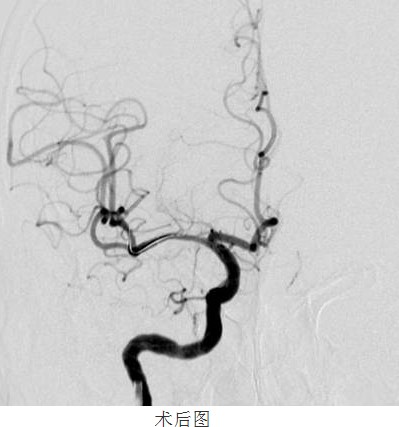

常規(guī)準(zhǔn)備后,神經(jīng)內(nèi)科顏津津主治醫(yī)師在助手高彬醫(yī)師配合下采用Seldinger法穿刺股動(dòng)脈,置導(dǎo)管鞘、引導(dǎo)管,在導(dǎo)絲帶引下將導(dǎo)引導(dǎo)管放置右側(cè)頸內(nèi)動(dòng)脈巖部造影,后在透視下,順著造影路圖,小心將微導(dǎo)絲、微導(dǎo)管通過狹窄處并置入右側(cè)大腦中動(dòng)脈M3段,接著撤出微導(dǎo)管,順著微導(dǎo)絲置入Gateway球囊, 至狹窄部位,經(jīng)造影骨性標(biāo)志等多重定位后證實(shí)球囊位置良好,接壓力泵緩慢加壓擴(kuò)張,撤出球囊造影,顯示血管成形良好。選取Wingspan支架, 順微導(dǎo)絲將支架輸送器小心送至狹窄處,造影定位確認(rèn)支架位置準(zhǔn)確覆蓋狹窄部位,釋放支架,撤出支架輸送器,造影證實(shí)血管狹窄處成形良好,觀察10分鐘后再次造影,支架無移位,狹窄處遠(yuǎn)端血管完整,未見血管狹窄、造影劑外滲。撤除導(dǎo)絲、導(dǎo)引導(dǎo)管,患者術(shù)后24小時(shí)可下床自行活動(dòng),術(shù)后1周順利出院,生活基本恢復(fù)正常,并叮囑梁伯繼續(xù)堅(jiān)持服藥,定期復(fù)診。

“大腦中動(dòng)脈血管成形及支架植入術(shù)”為我院首例顱內(nèi)支架植入手術(shù),其順利完成,標(biāo)志著我院在神經(jīng)介入診療方面的水平又上了一個(gè)新的臺階!